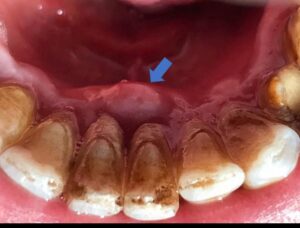

– Si kalon infeksioni nga goja në gjak Sëmundjet periodontale,si gingiviti dhe periodontiti ,shkaktohen nga baktere të cilat grumbullohen rreth mishrave dhe dhembëve .Kur mishrat janë të gjakosura dhe të inflamuara,këto baktere futen në qarkullimin e gjakut dhe nëpërmjet tij shkojnë në organet e tjera !